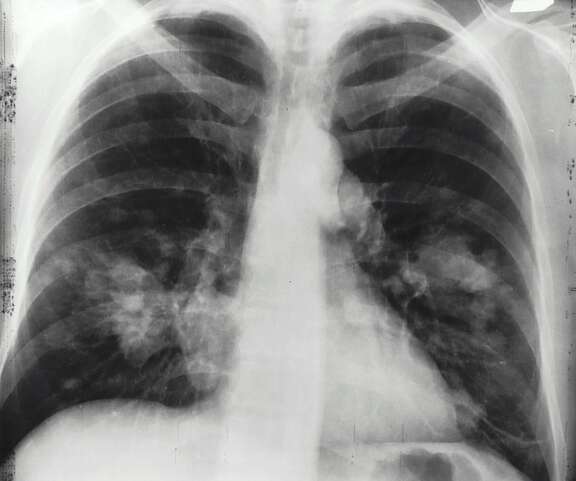

- ein Röntgenbild deines Brustkorbs oder eine Computer-Tomografie (CT) anordnen.

Bildgebende Untersuchungen

Es handelt sich dabei um:

- Computer-Tomografie (CT),

- Positronen-Emissions-Tomografie (PET-CT) oder

- Magnetresonanz-Tomografie (MRT).

Für diese Untersuchungen musst du in ein Spital oder eine radiologische Einrichtung gehen. Die Untersuchungen sind schmerzlos und dauern bis zu eineinhalb Stunden.

Mit den bildgebenden Untersuchungen beantwortet der Arzt folgende Fragen:

- Wo ist der Tumor?

- Wie gross ist er?

- Sind Lymphknoten befallen?

- Sind Metastasen vorhanden?